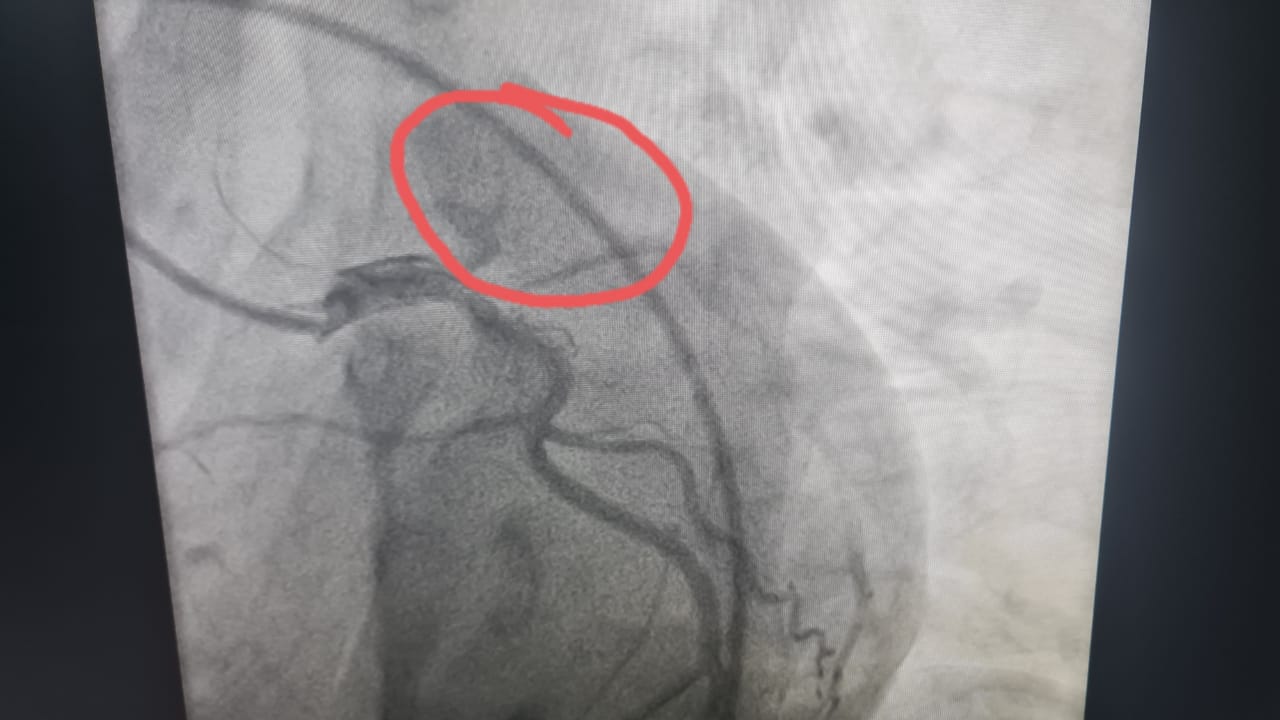

وبعد إجراء رسم القلب والفحوصات الطبية اللازمة، تبين إصابته بجلطة حادة في الشريان الأمامي الرئيسي.

وعلى الفور، قرر الفريق الطبي إجراء قسطرة قلبية عاجلة، حيث تم اكتشاف انسداد تام بالشريان الأمامي، وتم فتحه وتركيب دعامة بنجاح كامل، مما أدى إلى استقرار حالة الشاب وإنقاذ حياته في اللحظات الحرجة.